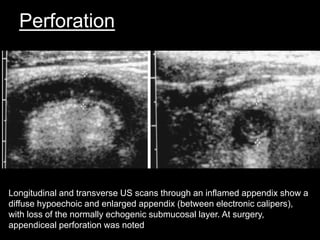

Perforation

Longitudinal and transverse US scans through an inflamed appendix show a

diffuse hypoechoic and enlarged appendix (between electronic calipers),

with loss of the normally echogenic submucosal layer. At surgery,

appendiceal perforation was noted